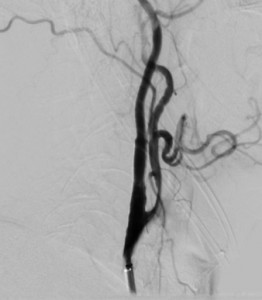

Mediante la realización de la Angiografía se constató la existencia de una ateromatosis carótida bilateral con una estenosis del 90% de ACID.

Diagnóstico final: Ictus isquémico por estenosis subtotal de arteria carótida interna

Con todos estos datos obtenidos de la anamnesis , la exploración y la realización del TAC, que nos orientan hacia la existencia de un proceso isquémico , provcocado por una defecto en el riego vascular cerebral y atendiendo a la urgencia de la situación se realizó angiografía cervicocraneal.

La angiografía por sustracción digital (ASD) es la técnica de referencia en el estudio vascular intracraneal y cervical. Los estudios angiográficos obtenidos con esta técnica se adquieren inyectando de forma directa contraste yodado en la luz arterial, por lo que se requiere la cateterización previa de la arteria de interés (52). Las ventajas de esta técnica son su elevada resolución espacial y temporal, la posibilidad de estudiar de forma selectiva y superselectiva un territorio arterial, la óptima delineación de la luz arterial y, sobre todo, la posibilidad de realizar procedimientos terapéuticos oclusivos o recanalizadores. La elevada resolución espacial y temporal de las imágenes obtenidas permite visualizar ramas distales de muy pequeño calibre y valorar la existencia de los diferentes tipos de circulación colateral.

El Doppler/ dúplex transcraneal y de troncos supraaórticos es un procedimiento muy sensible y especiífico que se realiza en todos los pacientes que han experimentado un ictus isquémico.. El estudio carotídeo nos permitirá diagnosticar la etiología aterotrombótica del ictus isquémico y valorar tratamientos preventivos específicos como la endarterectomía carotídea. Sin embargo en este caso debido a la gravedad de la oclusión y a los criterios que cumple el paciente se decide realizar un angiografía cerebral , con el fin de localizar con la mayor exactitud la lesión y guiado por dicha técnica realizar el procedimiento de revascularización, ya que presenta contraindicación de tratamiento quirúrgico y debido al grado de estenosis el tratamiento fibrinolítico no es una opción terapéutica válida.

Los neurorradiólogos guiados por la angiografía cerebral , realizan el procedimiento sin incidencias. Colocando un stent en carótida izquierda y permitiendo de esta manera la revascularización de la zona. El paciente permanece ingresado durante 24 horas en unidad de ictus sin complicaciones sintéticas, neurológicas, ni en punto de punción. Finalmente en situación de estabilidad clínica se decide traslado a su hospital de referencia para continuar cuidados médicos.